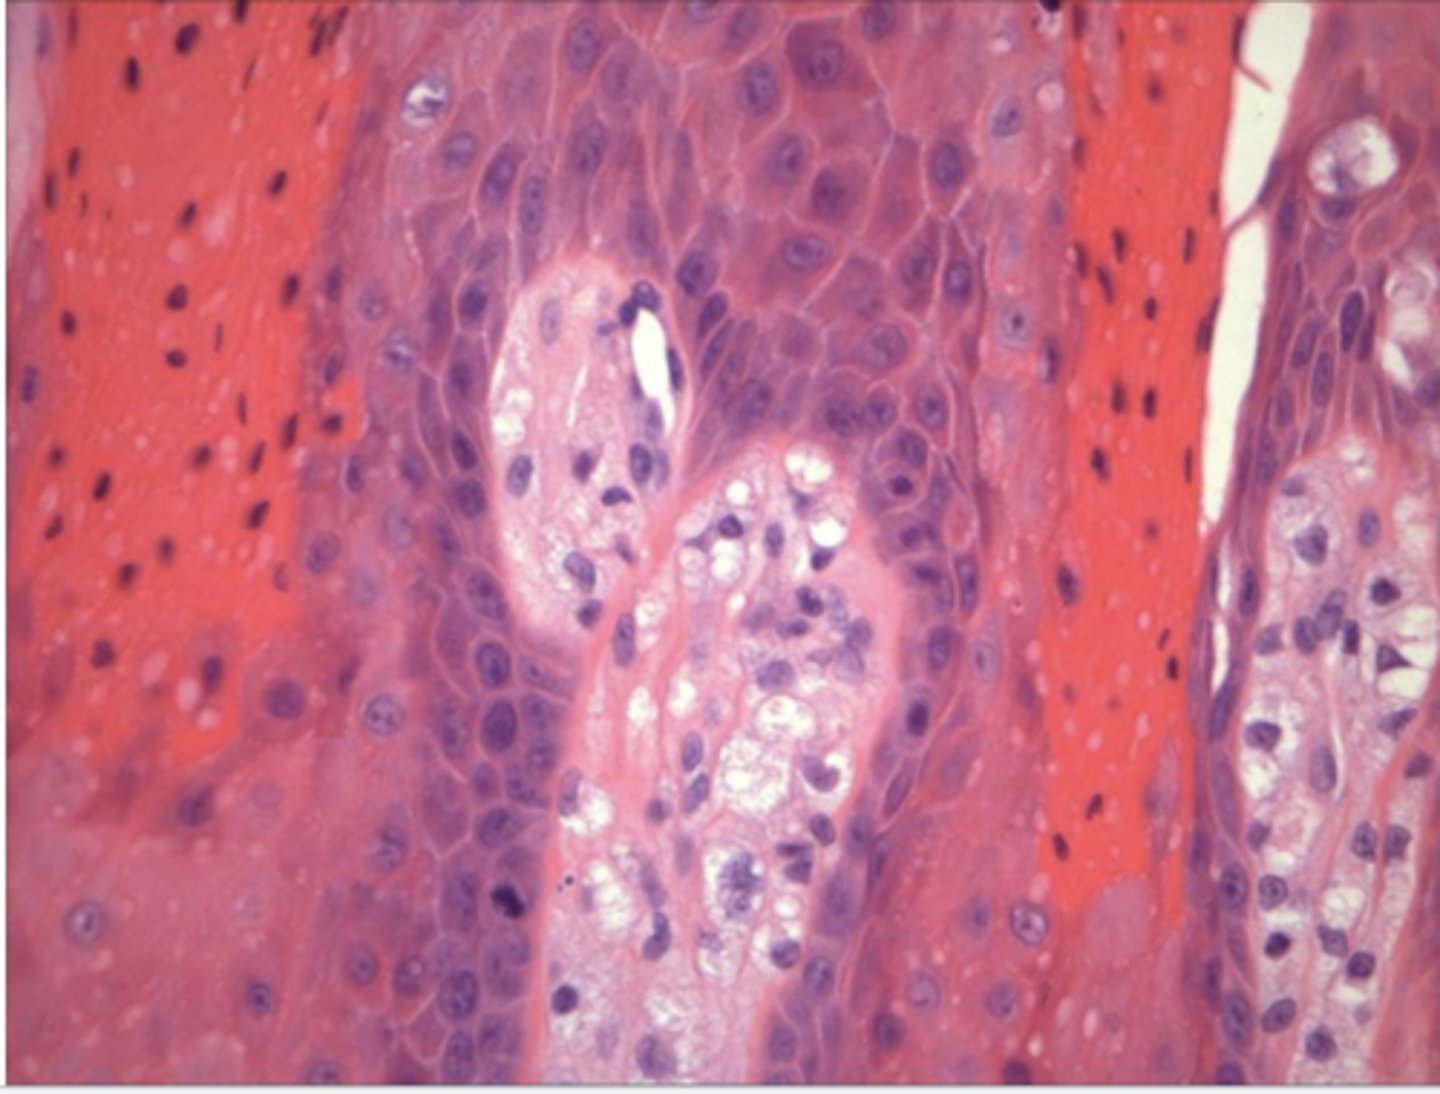

the following describe the histopathological features of what?

-hyperparakeratosis or hyperorthokeratosis

-papillary hyperplasia &/or pseudoepitheliomatous hyperplasia

-hyperplasia or connective tissue

epulis fissuratum

why can an histological image of pseudoepithliomatous hyperplasia be mistakenly diagnosed as squamous cell carcinoma?

histo of epulis fissuratum has pseudoepitheliomatous hyperplasia that resemble cancer b/c rete pegs running thru the horizontal plane & we may be unable to see connection to surface due to the orientation of the section we're viewing --> so it looks like de novo formation of epithelia w/ CT = suspicion for cancer